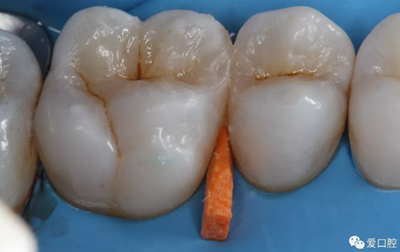

2. 接觸區(qū)恢復(fù)不良

( 1 )原因

充填體與鄰牙的鄰接區(qū),在形狀、位置、大小和牙間楔狀隙的形態(tài)上存在異常。如:無接觸或接觸點面積過大、過小、充填體邊緣嵴與鄰牙邊緣嵴高度不一致,鄰牙邊緣嵴缺損等。

( 2 )臨床表現(xiàn)

患牙區(qū)食物嵌塞,牙齦乳頭紅腫或萎縮。

( 3 )處理

磨改鄰面充填體形態(tài);磨改鄰牙;去除舊充填體,使用鄰面解剖式成型系統(tǒng)重新充填;嵌體、高嵌體、冠修復(fù)。